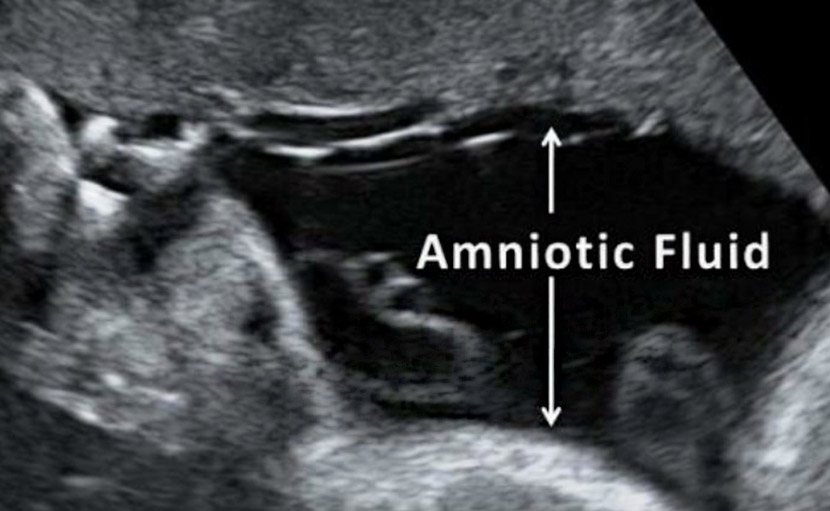

গর্ভাবস্থায় পানি ভাঙ্গা সম্পর্কে কতটুকু জানেন?

0 SHARES Share Tweet গর্ভাবস্থায় পানি ভাঙ্গা সম্পর্কে সঠিক ধারণা আমাদের অনেকেরই নেই। সাধারণত অ্যামনিওটিক মেমব্রেন রাপচা...